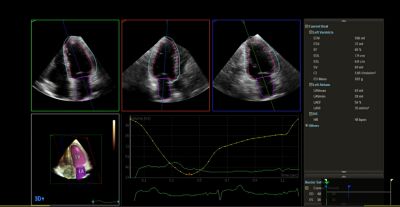

Ultrasound Workspace, TOMTEC, with 3D Auto RV image, EPIQ CVx

Experience flexible workflows

Ultrasound Workspace is a cardiovascular viewing, analysis and reporting system built on the legacy of the TOMTEC-ARENA platform. With a consistent set of on- and off-cart AI-driven image analysis and quantification tools, access to archived legacy data and off-cart vendor neutral analysis capabilities, it allows clinicians to leverage unified diagnostic workflows from the ultrasound exam room to the reporting room and beyond, wherever echocardiography data needs to be reviewed and analyzed.